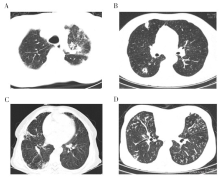

24例患者住院期间均进行了胸部CT检查。其中18例(75.0%)有较典型的肺诺卡菌病的影像特征, 如实变、肿块、结节、空洞、支气管扩张等, 15例(62.5%)有空洞, 13例(54.2%)有结节或团块影, 16例(66.7%)有支气管扩张。树芽征(23例, 95.8%)及磨玻璃影(20例, 83.3%)等非特异性影像在CT中极为常见, 少量胸腔积液8例(33.3%), 蜂窝间质改变4例(16.7%)。大部分CT显示双肺病变, 多种征象同时存在。患者初期影像表现为结节、团块或实变, 随着病情加重多形成空洞。见图3。